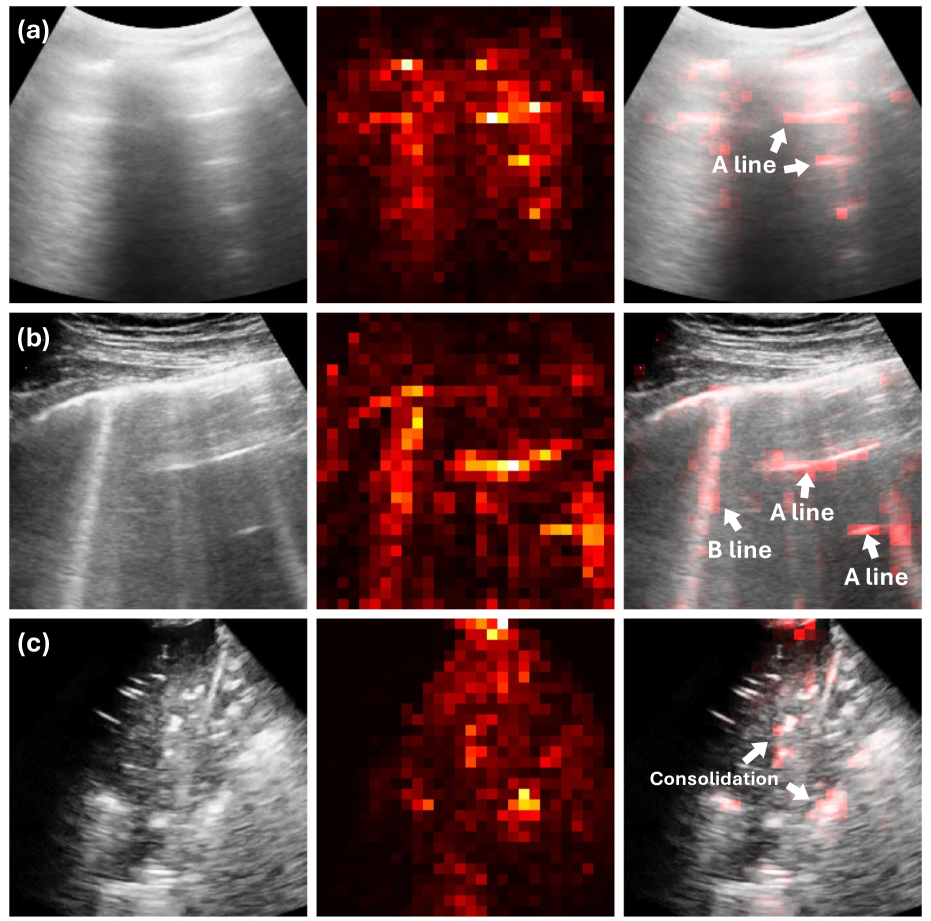

We evaluated MeDiVLAD at the frame level. For this, we trained a ResNet-50 (23.5M) as a classification baseline with a similar number of parameters to the ViT-S (21.7M) we used. The average scoring accuracy (k-NN/linear classifier) and ROC-AUC (one-vs-all) were reported. It should be noted that the k-NN accuracy is only provided for the models that were not fully supervised during training. In the upper half of Table 2, we first examined the impact of self-distillation. Without using LUS data, ResNet-50 pretrained on ImageNet (IMG) showed slightly lower classification accuracy than the other two DINO experiment sets, with the advantage of DINO becoming more pronounced after incorporating unlabeled ultrasound data. As expected, after finetuning the model with labeled frames, both accuracy and ROC-AUC improved, outperforming all other baselines (AUC: 0.9170.9170.9170.917 & Acc: 82.47%percent82.4782.47\%82.47 %). Remarkably, even without supervised finetuning, we achieved an accuracy of 75.05%percent75.0575.05\%75.05 %, surpassing the 71.94%percent71.9471.94\%71.94 % accuracy of the fully supervised ResNet-50. In Fig. 3, we present several attention map visualizations from the finetuned backbone. In (a) and (b), the attention maps accurately highlight both A-lines and B-lines, while in (c), the model identifies all regions of consolidation, offering clear insights into its decision-making process for LUS scoring.

Refer to caption

Fig. 3: Typical visualization of attention maps extracted from our pretrained ViT-S/8 (after finetuning).